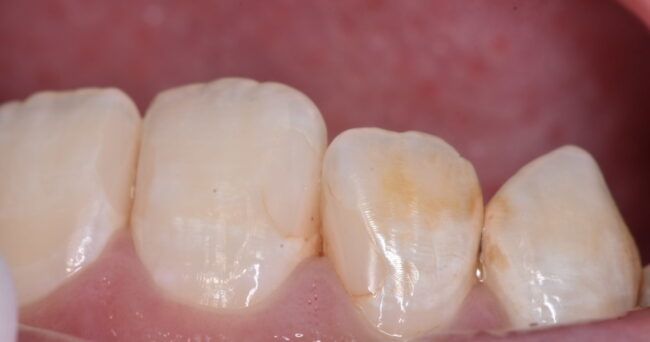

今回は歯と歯の間の虫歯です。むしろ、今回「も」ですね(´・_・`)

解説を入れずに写真を並べてみようと思います。それでは、下の写真をご覧ください。

おそらく、3つ目の写真で虫歯を取り終わったと思う方が多いのではないでしょうか?正確には4つ目が取り終わりです。

3つ目よりも4つ目の方が歯が白いのがわかるでしょうか?実際には4つ目の方が削っているので、深いわけです。深い、ということは写真を撮る時に暗くなりやすいはずです。それにも関わらず、4枚目の方が明るい=3枚目の汚染されている範囲が広い、ということです。